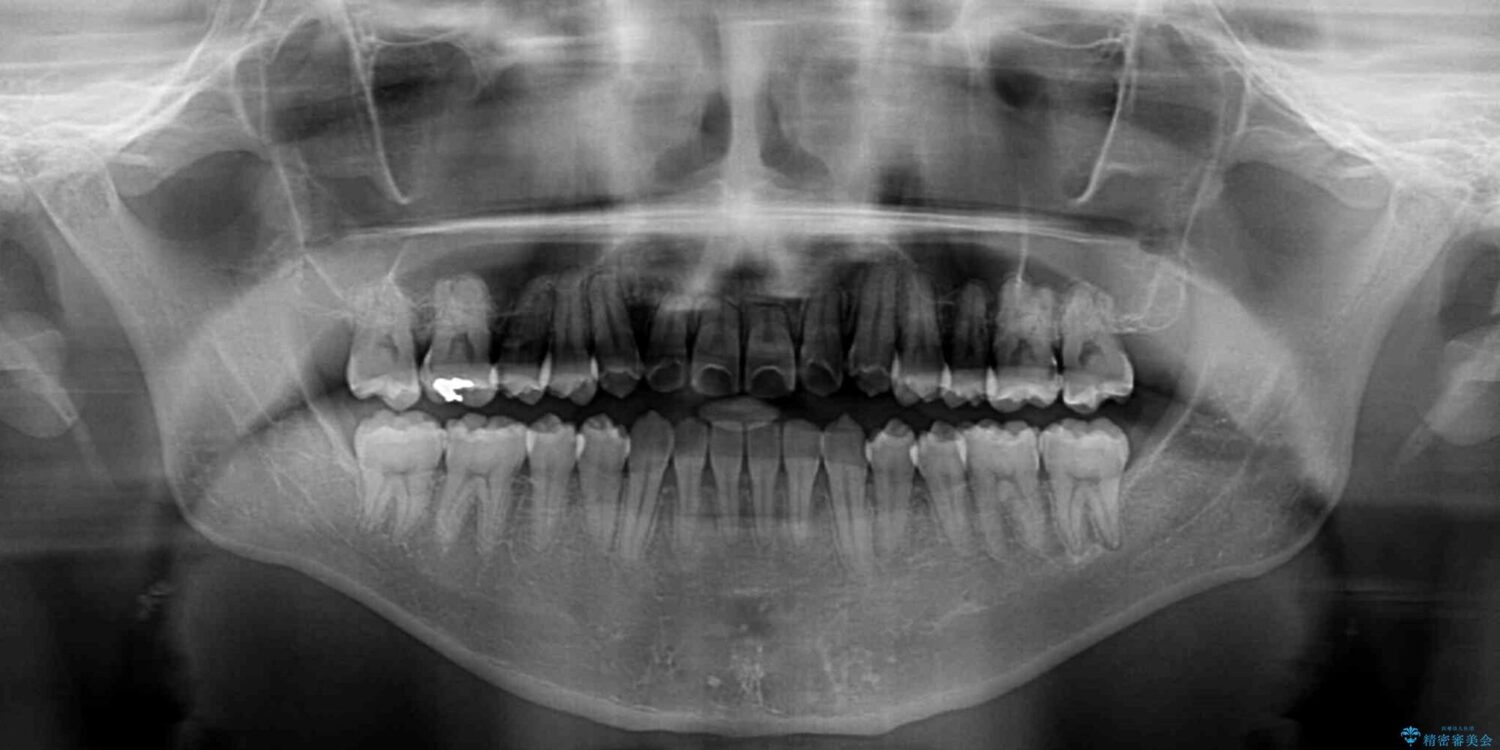

治療前

• 左右の八重歯が気になる ワイヤー装置での咬み合わせ改善 治療前画像